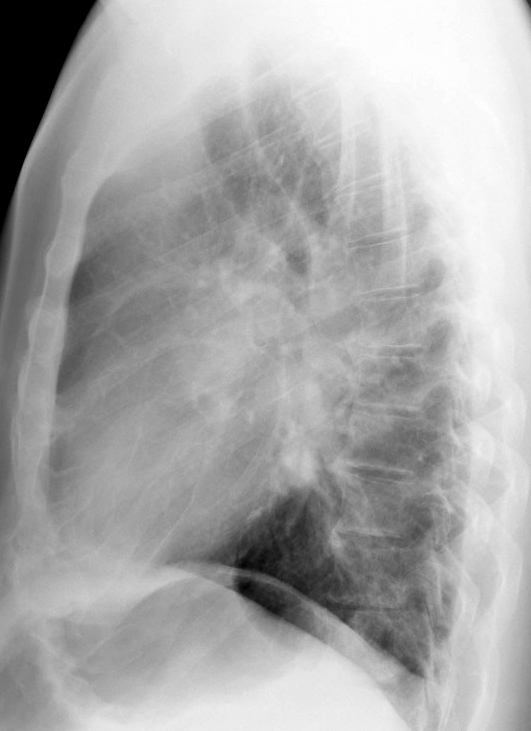

Bronch Cyst 1 Lat

Date: 05/11/2004